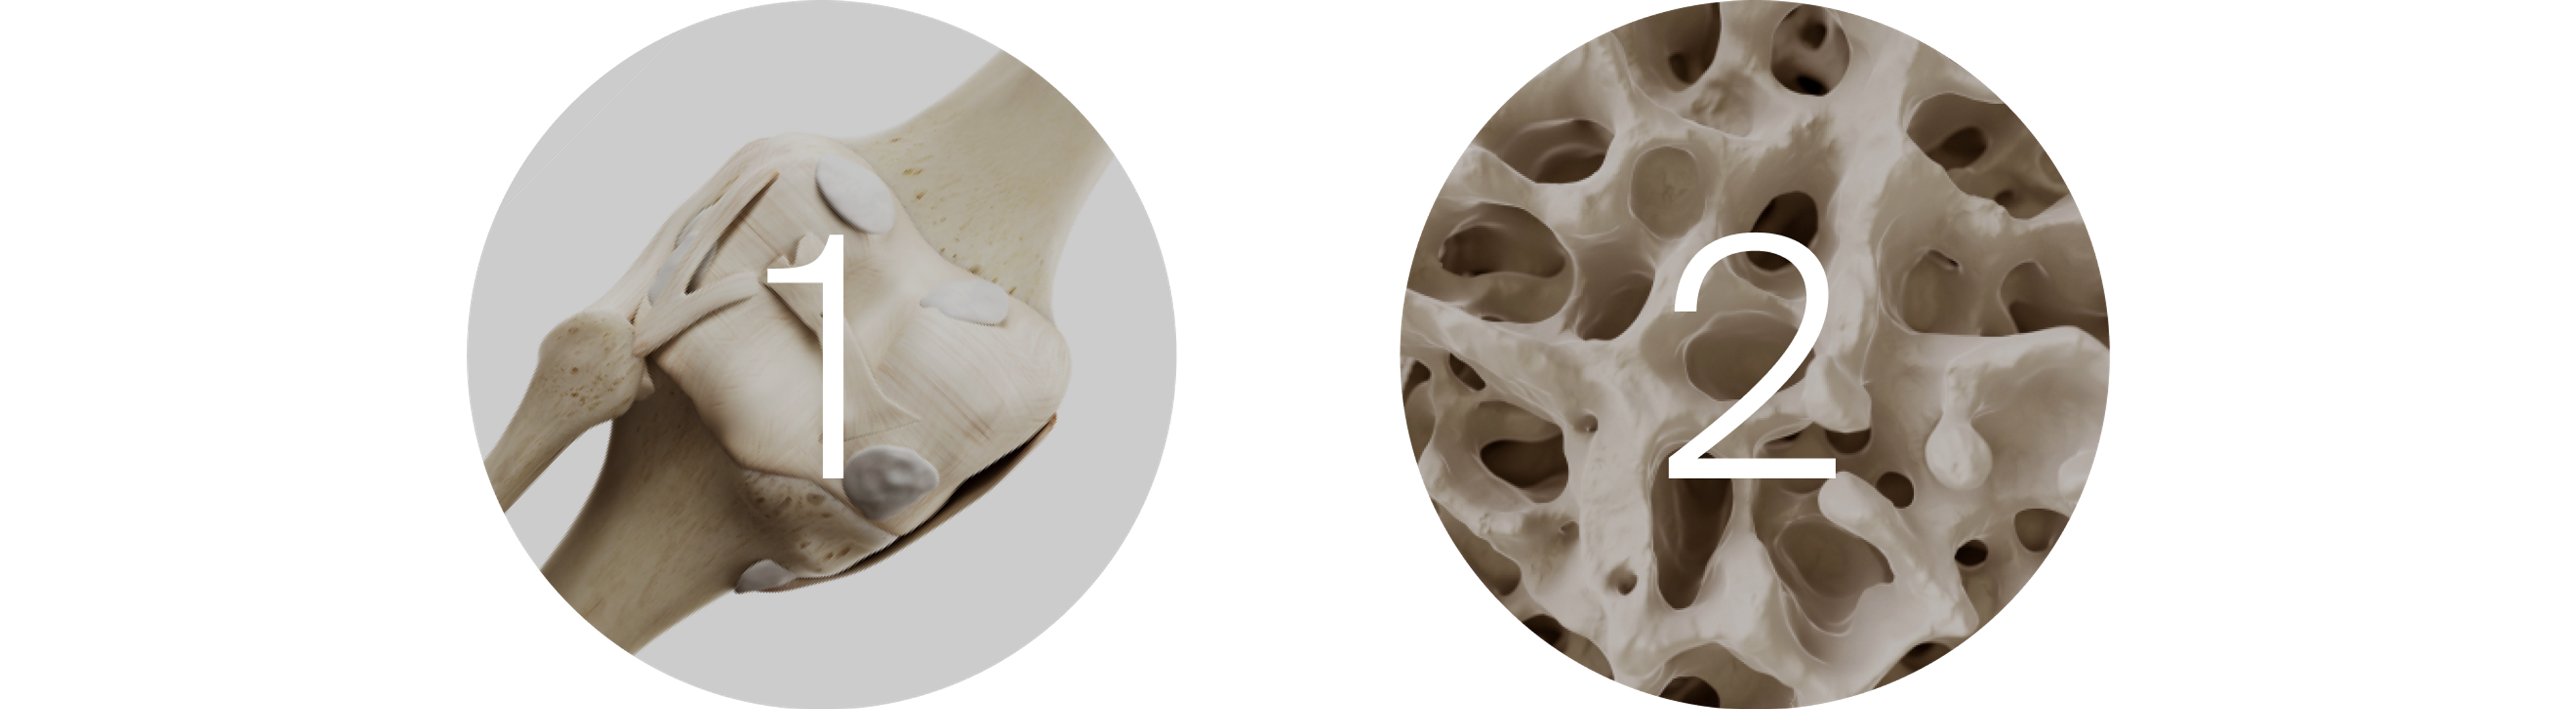

Joint Health

Mitochondrial dysfunction has been implicated in the development of different types of arthritis.[2] This year, a pre-clinical trial investigated how Urolithin A’s ability to promote mitophagy may impact cells with osteoarthritis.

Urolithin A Improves Mitochondrial Health in Osteoarthritis Pre-Clinical Models

Mitochondrial decline and reduced levels of mitophagy are commonly seen in cartilage cells contributing to the progression of osteoarthritis. This pre-clinical trial demonstrated the ability of Urolithin A to improve mitochondrial health in these cells, protect against cartilage degradation and reduce arthritic pain and inflammation in disease models.

1. Urolithin A administration increased mitophagy in knee cells from both healthy donors and donors with osteoarthritis.

2. In mouse models of osteoarthritis, Urolithin A supplementation protected against cartilage damage, improved joint inflammation, and reduced pain levels.

Osteoarthritis is the most common age-related joint disorder contributing to debilitating pain and immobility, and the results of this trial establish the connection between mitochondrial health and osteoarthritis. This trial demonstrates the need for human studies to investigate the role Urolithin A may play in osteoarthritis.